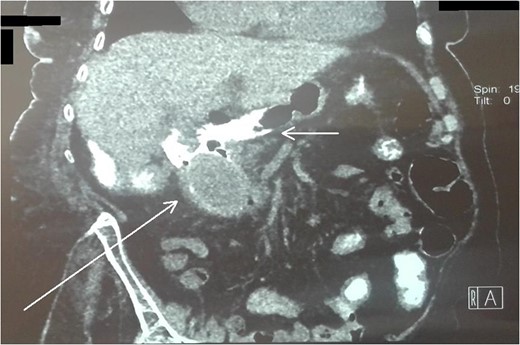

An 87-year-female patient was admitted to emergency department complaining about vomiting for the past 7 days with mild abdominal pain. The patient was hemodynamically stable, had sluggish bowel sounds and soft abdominal wall with mild tenderness. The patient also suffered from atrial fibrillation, heart failure, myelodysplastic syndrome, hiatus hernia and cholelithiasis. The findings of the laboratory tests were unremarkable. Plain chest and abdominal radiograms revealed hiatus hernia with gastric dilation (Fig. 1), a few air-fluid levels and pneumobilia, with delineation of extrahepatic and intrahepatic bile ducts by air (Fig. 2). A nasogastric tube was inserted, which drained biliary content. An abdominal computed tomography (CT) scan revealed the presence of air in the intrahepatic bile ducts, free air and leakage of oral contrast agent in the hepatic hilum and subhepatic space and an impacted gallstone in the third portion of the duodenum (Figs 3 and 4). The diagnosis of cholecystoenteric fistula and proximal gallstone ileus was set.

Abdominal CT scan (coronal plane). The long arrow shows the impacted gallstone and the short arrow shows the free air and the leakage of oral contrast agent.